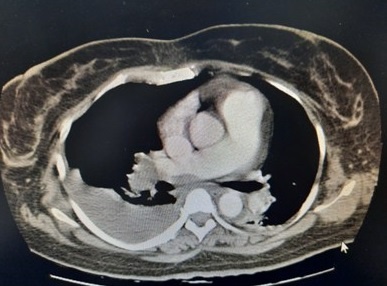

CT scan ngực có cản quang của người bệnh. Ảnh: BVCC.

Chụp CT scan ngực có cản quang, bác sĩ phát hiện bệnh nhân N. bị tràn dịch màng phổi 2 bên, tràn dịch màng ngoài tim lớp dày khoảng 14 mm. Các bác sĩ chẩn đoán thuyên tắc phổi nhóm trung bình cao, huyết khối tĩnh mạch đùi nông và khoeo bên trái, thiếu máu mức độ nặng do u xơ tử cung gây cường kinh.